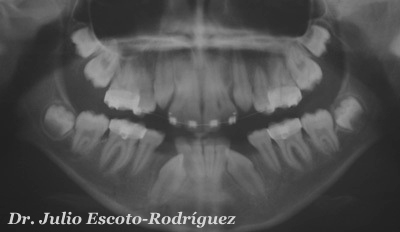

Radiografía panorámica de una paciente femenina de 16 años de edad, sana, antecedentes heredo-familiares negados. Referida por su odontólogo para tratamiento de ortodóncido/quirúrgico por presentar falta de espacios y caninos superiores e inferiores retenidos.

Seis meses después se puede observar ambos caninos superiores colocados

en su posición correcta en sentido vertical. Nótese los márgenes cervicales

de ambos caninos dentro de los parámetros de normalidad, sin ningún tipo

de retracción.

| Caso terminado. Ahora en período de retención. Control radiográfico 10 meses después de retirados los aparatos fijos de ortodoncia. |